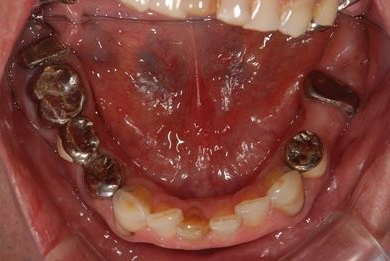

治療前

• 治療前